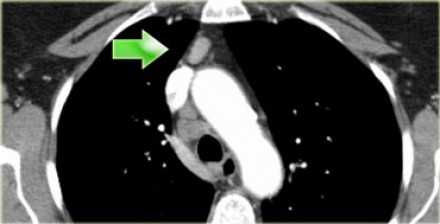

На ниже представленном КТ снимке визуализируется некроз лимфатических узлов группы IA.

На ниже представленном КТ снимке визуализируется лимфаденопатия группы IB справа.

На ниже представленном постконтрастном КТ снимке представлен пациент с карциномой языка и лимфаденопатией II группы лимфатических узлов.

На ниже представленном постконтрастном КТ изображении визуализируется увеличение и контрастное усиление лимфатических узлов III группы.

На постконтрастном изображении белой стрелкой указан увеличенный лимфатический узел IV группы. У пациента удалена правая доля щитовидной железы и правая яремная вена, что указано чёрной стрелкой, всвязи с папиллярной карциномой.

На постконтрастном изображении белой стрелкой указан увеличенный лимфатический узел V группы.

На постконтрастном изображении белой стрелкой указан увеличенный лимфатический узел VI группы.